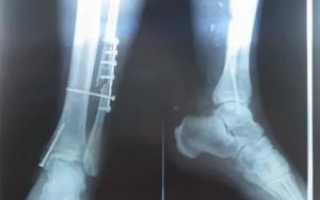

Наиболее часто врачи назначают рентгенологическое обследование и производство снимков. Методика позволяет диагностировать перелом большой и малой берцовой кости. При повреждении нерва показана электронейромиограия.

Если перелом в области мыщелков или оскольчатый показано проведение МРТ. Методика позволяет уточнить вид перелома, особенно если перелом большой берцовой кости без смещения, невидимый на рентгеновском снимке.

Если костные отломки занимают анатомическое положение, доктор обезболивает место травмы с помощью внутримышечного ввода препаратов, после чего от пяточной кости и чуть выше, чем до середины бедра накладывается гипсовая повязка. После наложения гипса врач делает повторный рентгеновский снимок, чтобы убедиться, что во время проведения процедуры не произошло смещение отломков.

На протяжении всего периода вытяжения больному делается рентген, на котором врач наблюдает, как образуется костная мозоль. При нормальном состоянии пациента, вытяжение отменяется приблизительно через полтора месяца, после чего кости фиксируются с помощью гипсовой лангеты. Спустя два — четыре месяца проводится контрольный рентген и снимается гипсовая повязка.

Если вытяжение не приносит должного результата, то больному назначается оперативное вмешательство, во время которого костные отломки фиксируются с помощью стержней, шурупов, пластин или аппарата Илизарова.